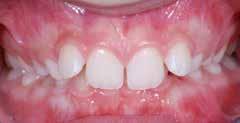

Frenuli delle Labbra

Nell’età della dentizione mista, di tutti i frenuli risulta importante soprattutto quello del labbro superiore (vedi capitolo 10). Il forte sviluppo di tale frenulo può causare la formazione di un distema mediale (Olivi et al. 2010). Per quanto concerne la diagnosi differenziale, la frenulectomia risulta indicata soltanto qualora il frenulo labiale presenti un’inserzione molto bassa e si fonda, sul lato palatale, con la papilla incisiva. Sotto il proflo radiologico, tra le radici degli incisivi superiori si osserva un’incisura che indica il passaggio interosseo delle fbre. La frenulectomia dovrebbe comunque venire effettuata solamente dopo l’eruzione degli incisivi laterali superiori Figg. 17-18

17,18 _

Frenuli labiali superiori.